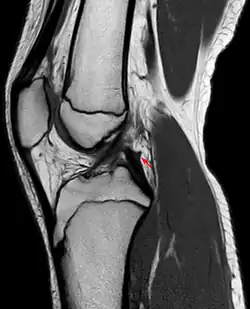

Posterior meniscofemoral ligament on MRI, sagittal -

Posterior meniscofemoral ligament (Wrisberg) behind the posterior horn of the lateral meniscus close to its insertion. Sometimes wrongly interpreted as a meniscal tear.